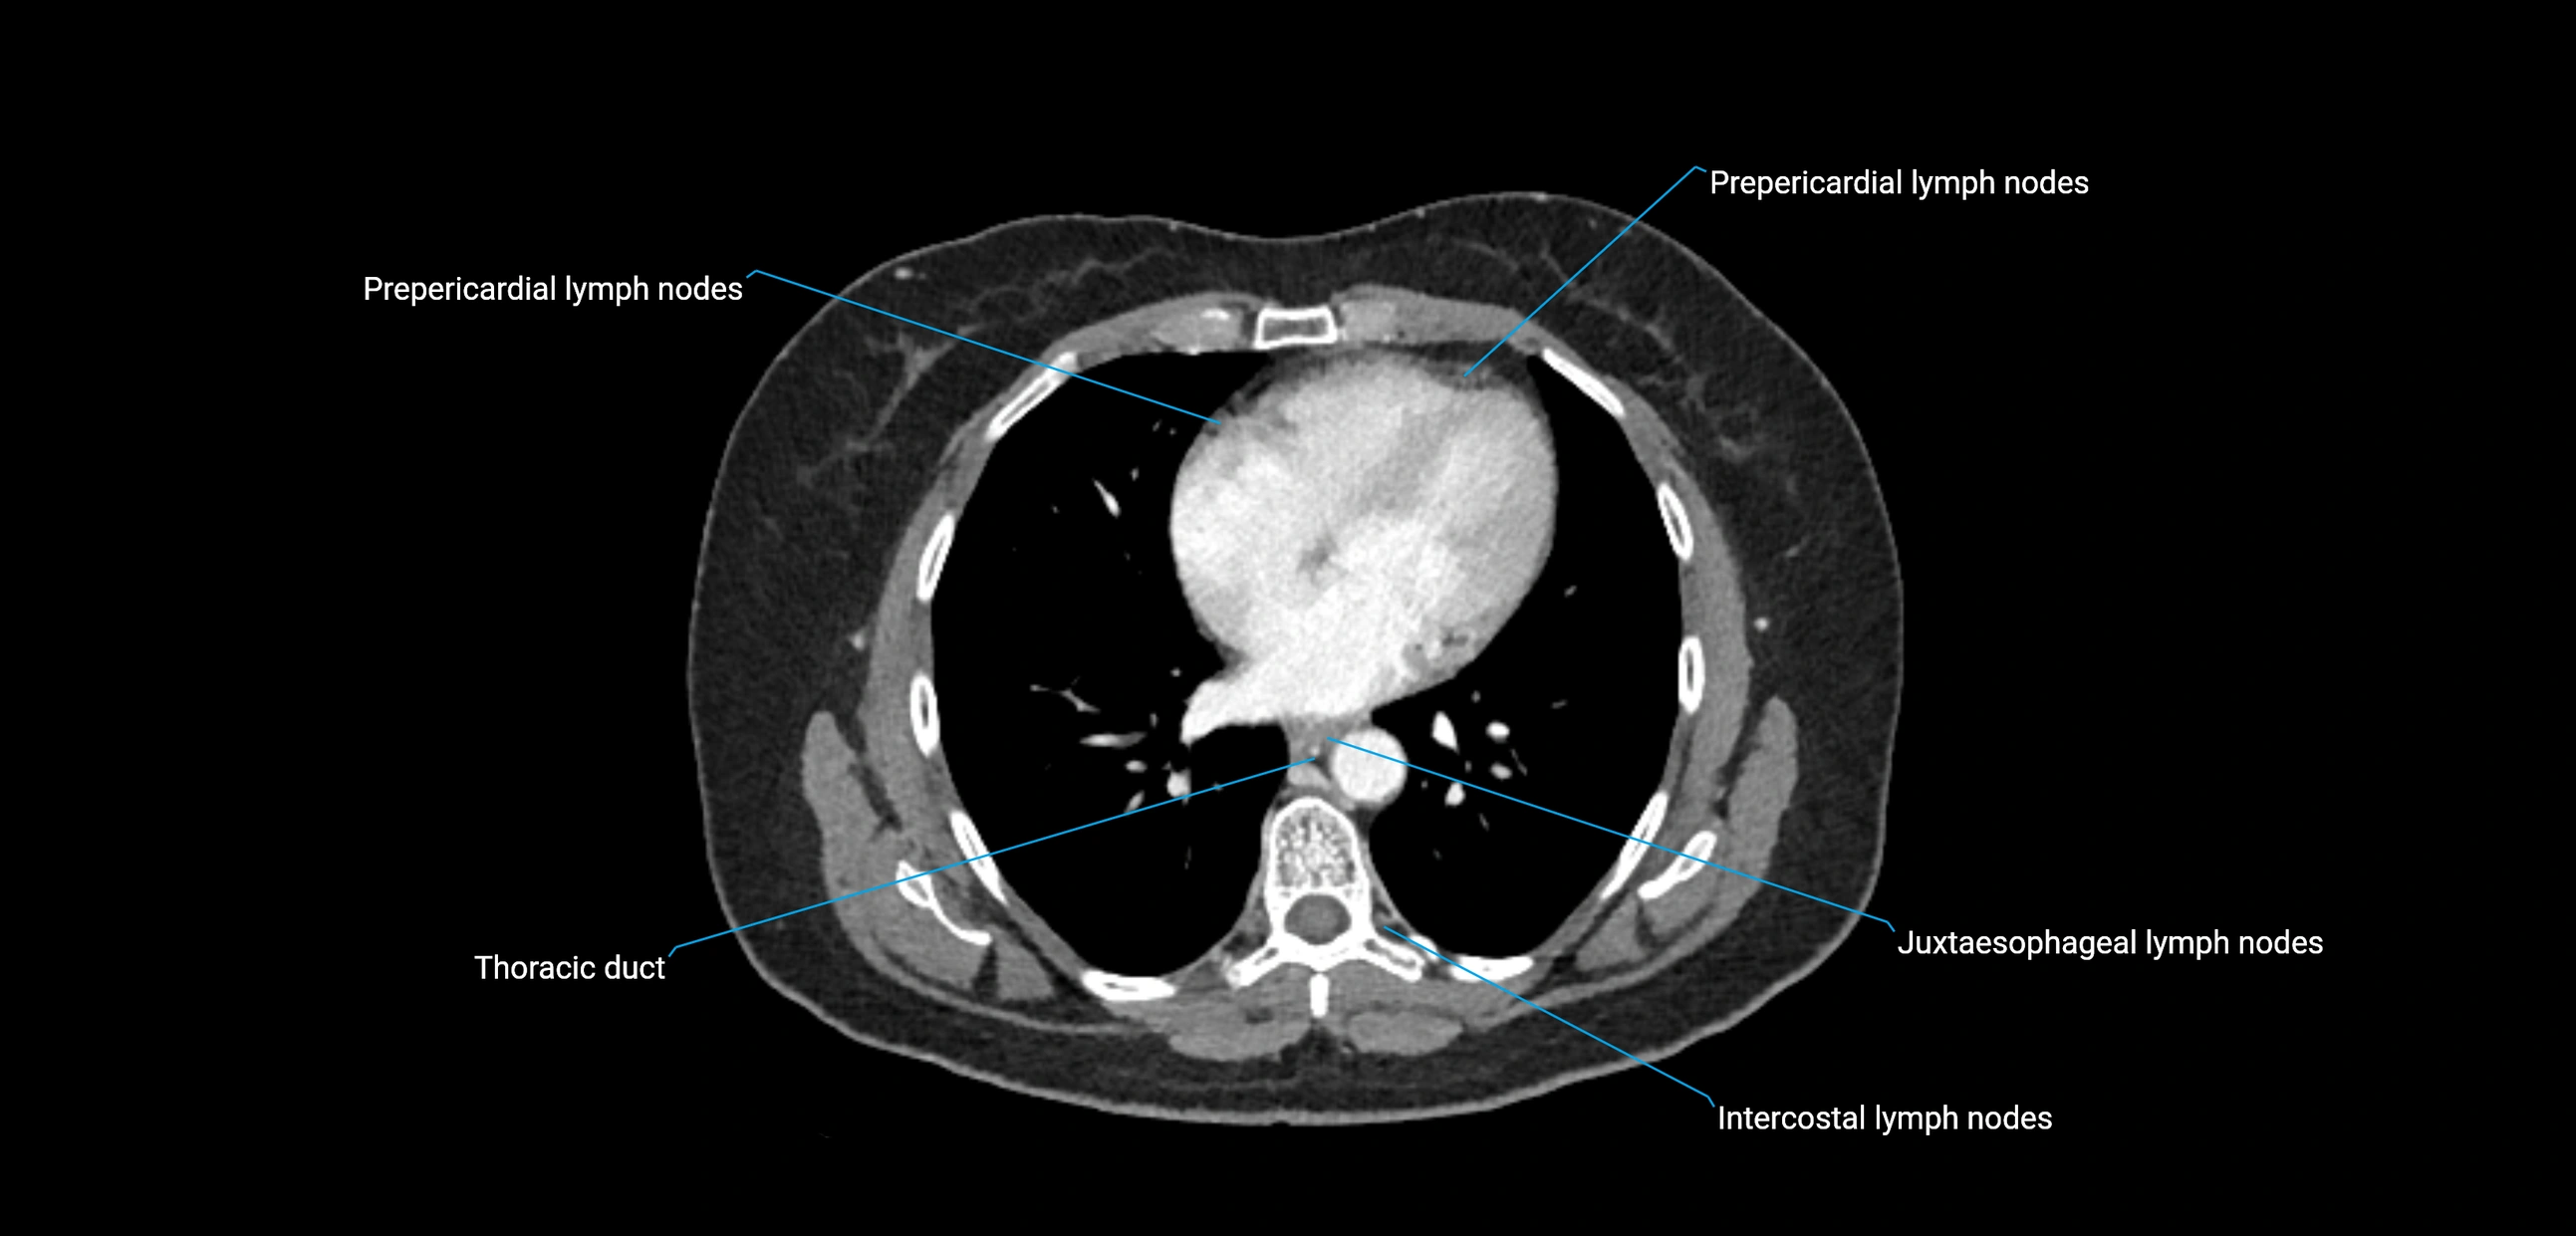

CT Appearance

CT Pre-Contrast:

• Nodes appear as soft-tissue density nodules adjacent to the aorta and IVC

• Calcification may be seen in chronic infections (e.g., tuberculosis)

CT Post-Contrast:

• Normal nodes enhance homogeneously

• Malignant nodes may show heterogeneous enhancement, central necrosis, or conglomerate formation

• Size >1 cm short axis is suspicious, though morphology and distribution are equally important